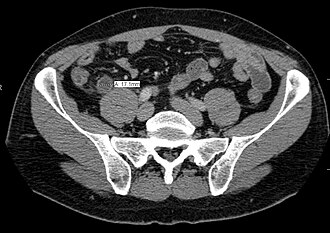

Računalna tomografija

CT abdomena je jedna od boljih dijagnostičkih metoda koja prikazuje prošireni crvuljak sa znacima okolne upale što predstavlja jedan od sigurnih znakova akutnog apendicitisa.